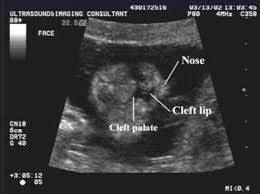

I may just be being paranoid bc i am a very paranoid person anyway. Involve the superficial tissues. Cleft lip may be detected with ultrasound beginning around the 13th week of pregnancy. Best seen on coronal images of the upper lip.

Best seen on coronal images of the upper lip. Type 2 unilateral. My ultrasound tech said that she can easily spot a cleft lip but a cleft palate is much harder to see i am sure you could google ultrasound pics with cleft lips and see some pictures. An explanation why the cleft was mistakenly considered to be one on the left side could be that the cleft was located near to the midline and the 2d ultrasound frontal view was an oblique frontal view figure 1.

Midline sagittal views normal. Ultrasound pic looks like cleft lip and im freaking out. Ultrasound of cleft lip and palate. What does cleft lip look like in ultrasound i think you can see it easily especially the 3d 4d one.